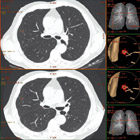

CT screening (rano otkrivanje) karcinoma pluća

Karcinom pluća je najčešći karcinom kod muškaraca,  pa se ranom otkrivanju te bolesti pridaje velika važnost. Uvođenje višeslojnog CT-a (MSCT) u kliničku praksu omogućilo je i screening (rano otkrivanje) karcinoma pluća. Pregled je namijenjen onima koji su visokog rizika za karcinom pluća i omogućava otkrivanje izrazito malih čvorova u plućima, koji mogu biti prisutni, a da nisu vidljivi na standardnom rtg snimku pluća. Rano otkrivanje ovih promjena može dramatično poboljšati uspješnost liječenja karcinoma pluća.

CT screening pluća se preporučuje uraditi pušačima starijim od 60g, a čiji pakovanje-godine index je veći od 10 (pakovanje-godine index se dobije tako što se pomnoži broj godina pušenja sa brojem kutija cigareta koje se ispuše svaki dan: preko 80% karcinoma pluća se dijagnostikuje u ljudi starijih od 60g). Drugi kandidati za pregled su pacijenti starosti 50-60g, koji imaju pakovanje-godine index 20-30 ili s drugim riziko-faktorima kao što je izlaganje azbestu ili hronična opstruktivna bolest pluća.

Šta mogu očekivati od rezultata testa?

Ako je screening CT uredan dalje ispitivanje nije potrebno.

Ako se nađe čvor u plućima, može biti potrebno uraditi detaljniji-dijagnostički CT pluća, s kontrastom. Često se za čvorove koji su nadjeni pri preventivnom pregledu ispostavi da su granulomi ili ožiljci kada se uradi detaljniji/dijagnostički CT pluca ili se radi o čvorovima benignih karakteristika, koji se potom prate u određjenim periodima da bi se bilo sigurno da se radi o zaista benignoj promjeni.